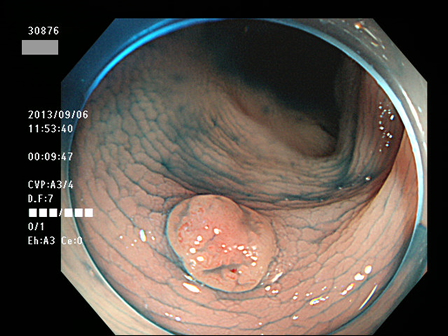

上記100名より抽出した平坦・陥凹型腺腫(=癌化の危険が高いが見落としやすい病変)の内視鏡写真

30801 30804 30805 30814 30819 30822 30823 30825 30827 30828 30829 30830 30833 30834 30835 30837 30838 30839 30840 30841 30843 30846 30848 30850 30853 30854 30855 30857 30858 30860 30862 30863 30867 30868 30870 30872 30873 30874 30875 30876 30882 30884 30886 30887 30891 30892 30893 30894 30895 30897 30898・・・・・・の52名